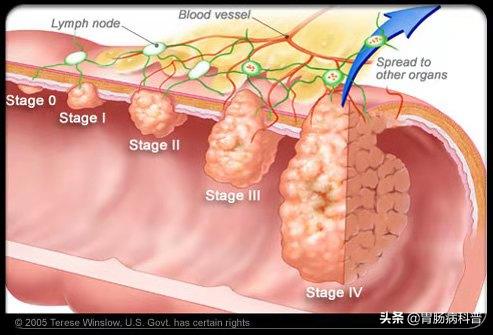

肠息肉演化为肠癌的过程需要5-15年

从正常粘膜到肠癌是个漫长的过程

结肠息肉与结肠癌的关系密切,大约80-95%的结直肠癌是结直肠息肉演变而来。

所以,临床上一经发现,一般都需要切除以绝后患。